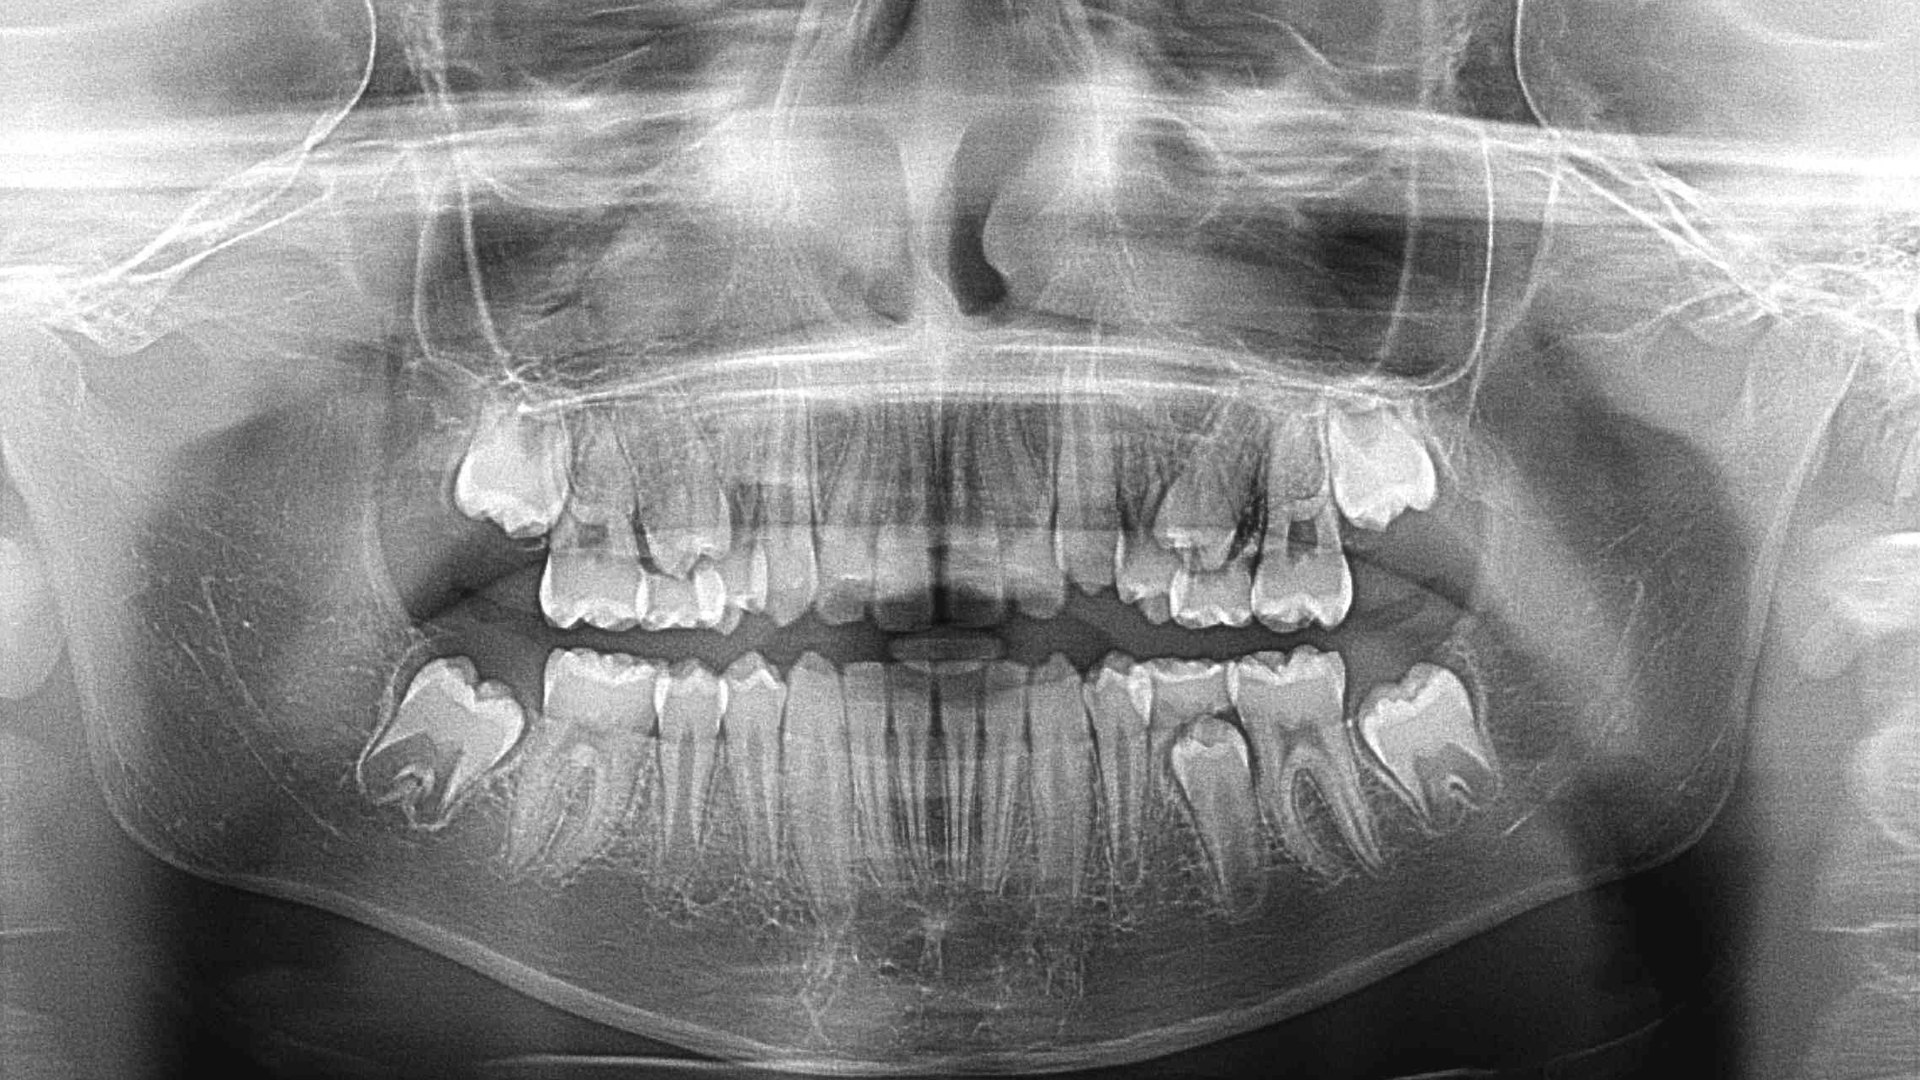

OPT – ortopantomografia

L’ortopantomografia, nota anche come ortopantomogramma o, più comunemente, “radiografia panoramica delle arcate dentarie”, è un esame radiologico che permette di analizzare contemporaneamente i denti, le arcate dentarie e le ossa di mascella e mandibola. Il tubo e la cassetta radiografica utilizzati nella procedura vengono fatti girare intorno alla testa del paziente.

A cosa serve l’ortopantomografia (OPT)?

L’ortopantomografia serve a studiare i denti, le ossa dei processi alveolari e la mandibola nei casi di problemi odontoiatrici. Permette inoltre di rilevare malformazioni dentarie, come denti inclusi o di identificare lesioni ossee, infiammazioni, cisti o tumori degli alveoli o nella mandibola.

Oltre che dall’odontoiatra, l’esame potrebbe essere prescritto anche da altri specialisti, ad esempio da un chirurgo, da un oncologo o da un otorinolaringoiatra.